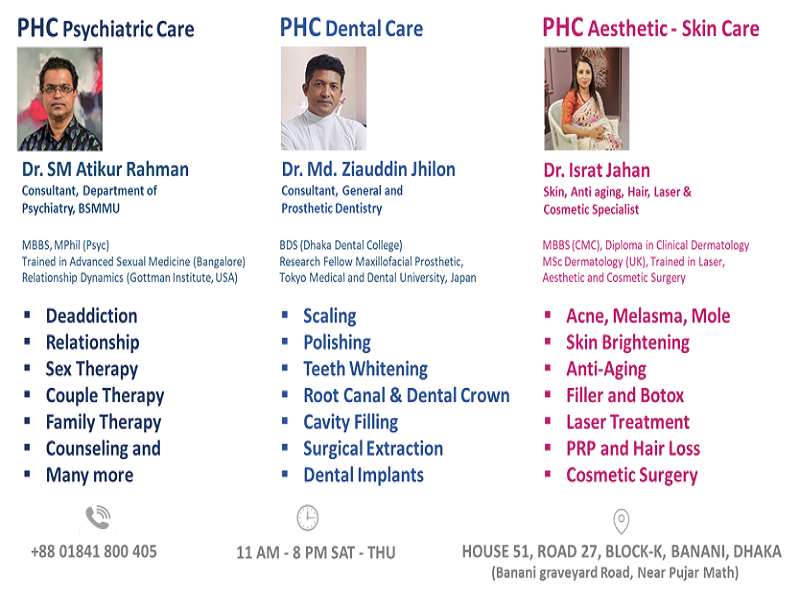

Departments

Doctors

Dr. Md. Ziauddin Jhilon

BDS (Dhaka Dental College) FMFP, Tokyo Medical and Dental University, Japan Specialized in Post Surgical Prosthetic Rehabilitation Specialized in Implantology Specialized Consultant of Prosthetic and General Dentistry

Dr Sifat Saba

MBBS, PGD(Skin & VD)USA Diploma in Aesthetic Dermatology (USA, CHENNAI) Fellowship in Advanced Laser & Skin Microsurgery (USA, DELHI) Trained in Trichology and Hair Transplant (India)